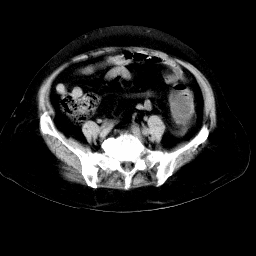

以下是引用arven在2008-11-9 10:13:00的发言:[br]肠壁增厚,形态较规则,支持降结肠炎症改变